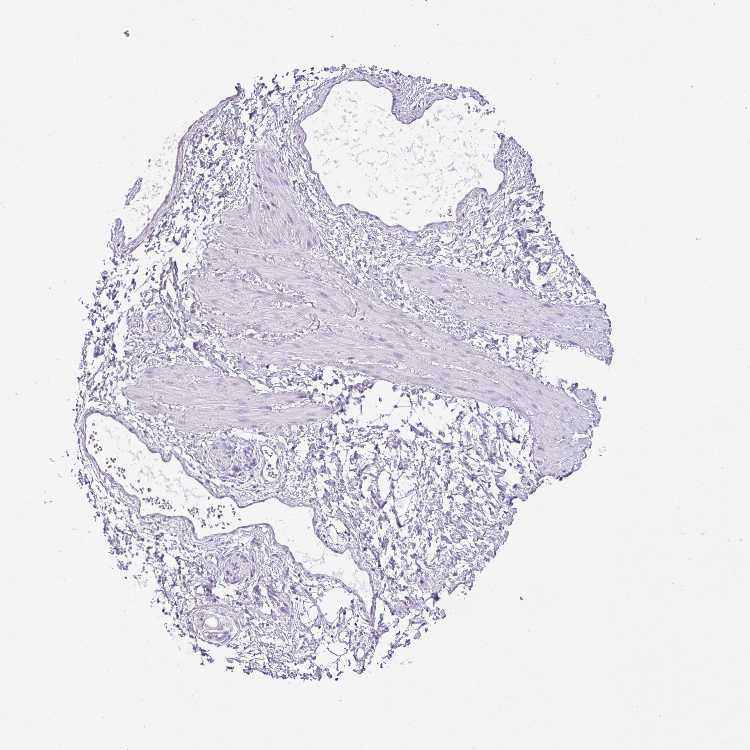

SOFT TISSUE 2 - Antibody stainingi

Antibody staining in the annotated cell types in the current human tissue is reported as not detected, low, medium, or high, based on conventional immunohistochemistry profiling in selected tissues. This score is based on the combination of the staining intensity and fraction of stained cells.

Each image is clickable and will lead to virtual microscopy that enables deeper exploration of all samples and also displays staining intensity scores, fraction scores and subcellular localization as well as patient and tissue information for each sample.

Antibody HPA019085Antibody HPA020456

Fibroblasts Not detectedNot detected

Peripheral nerve LowNot detected